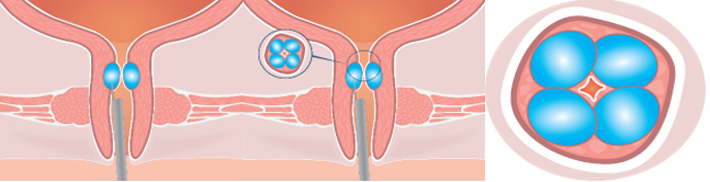

Bulkamid hydrogel tedavisi hastaya genel ya da lokal anestezi verilmesi ile üretal duvar üzerinde üç ila dört yere bezelye büyüklüğünde bir dizi enjeksiyonla yapılmasından ibarettir. Yaklaşık 5 ila 10 dakikalık bir zaman diliminde, kesik yapılmadan gerçekleştirilen bu tedavi kadınlarda idrar kaçırma problemini kalıcı şekilde ortadan kaldırır.